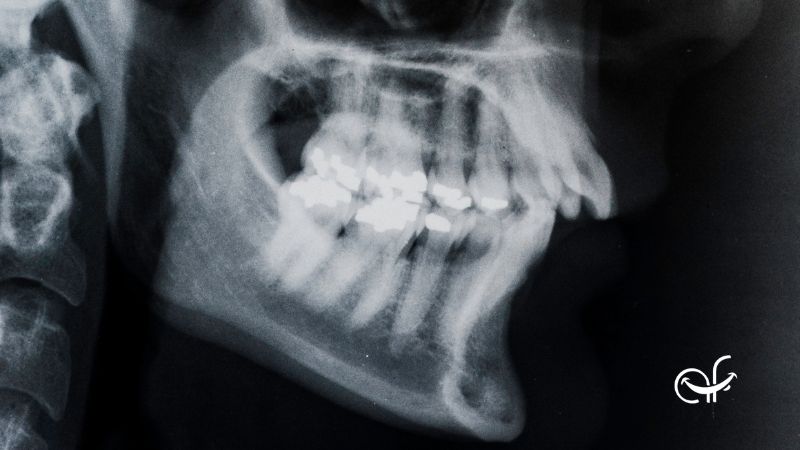

Cuando hablamos de mandíbula retraída nos referimos a una posición en la que la mandíbula inferior está más hacia atrás de lo normal con respecto al maxilar superior. Esto puede afectar a la forma en la que encajan los dientes y a la relación entre las estructuras de la cara.

A nivel clínico, esta situación también se conoce como retrognatia mandibular, un término más técnico que describe ese retraso mandibular en relación con el resto del rostro. No significa necesariamente que exista un problema grave, pero sí una alteración estructural que conviene valorar dentro del contexto de cada persona.